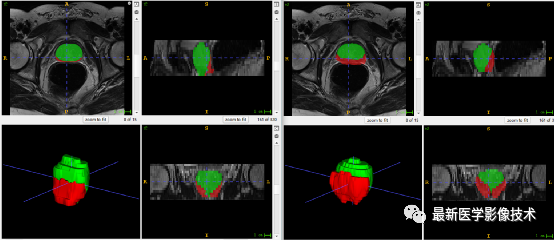

5、验证集分割结果

左边是金标准结果,右边是网络预测结果。